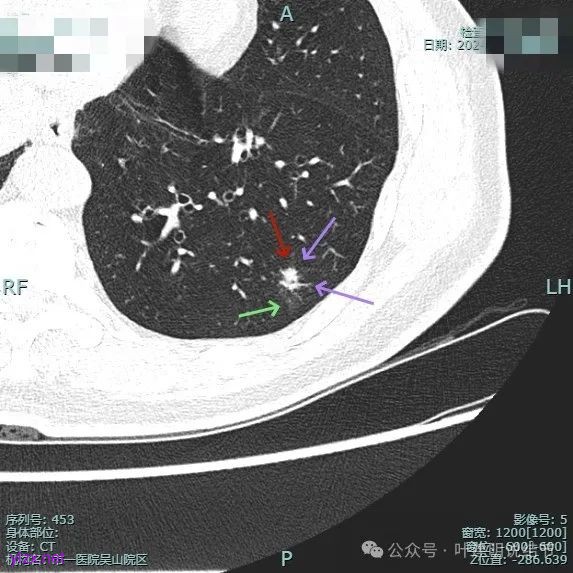

整体纵向仍偏长条些,实性部分不太致密,边上磨玻璃成分的轮廓与界限不太清楚,毛刺显得长。

仍有支气管扩张,但较2024年时密度感觉低了点。

密度较淡且缺乏收缩力。

密度杂乱,血管进入,但血管说不上明显异常增粗,磨玻璃成分淡而瘤肺界限欠清。

总体较之前密度有减低,缺乏聚拢性。

我考虑较前好转,应该是慢性炎,建议9个月后再复查。